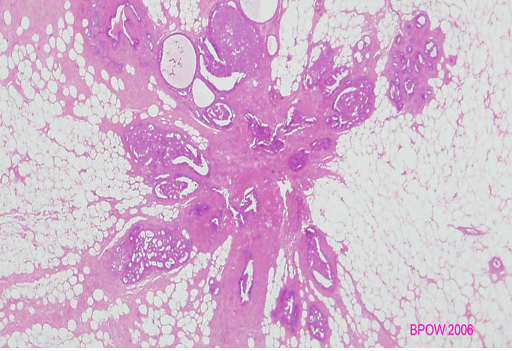

Q

What is this?

A

Radial scar - histology

Some hypoxia and trauma, exaggerated response. Stellate architecture. Needs to be excised as it can harbour malignant cells → tubular carcinoma